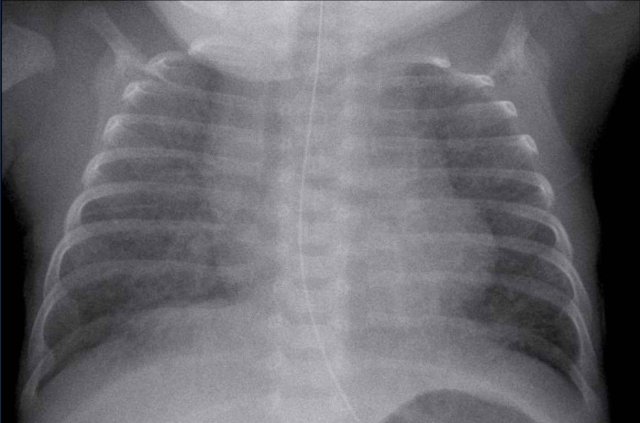

A full term neonate, with respiratory distress after 24 hours.

Image

Hyperinflation of both lungs and cardiac enlargement with increased interstitial markings and vascular markings. No pleural fluid.

The differential diagnosis includes TTN and neonatal pneumonia. After 48 hours there was no improvement of the respiratory distress, and the neonate developed signs of infection.

One might argue that there could be a combination of TTN and pneumonia.